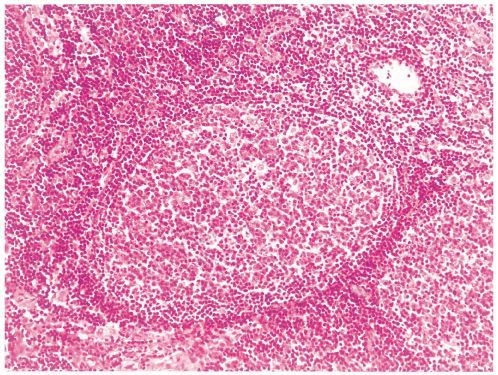

42歳の男性。頸部のリンパ節腫大を主訴に来院した。数年前から風邪をひきやすいと感じていた。1年前から両側の頸部にリンパ節腫大を自覚していた。自宅近くの医療機関を受診したところ,右頸部リンパ節の生検で悪性腫瘍が疑われたため紹介されて受診した。両側の頸部に径3cmのリンパ節を数個触知する。右頸部に生検跡を認める。両側の腋窩に径2cmのリンパ節を1個触知する。脾を左肋骨弓下に3cm触知する。血液所見:赤血球302万,Hb 9.2g/dL,Ht 30%,白血球30,500(桿状核好中球3%,分葉核好中球3%,単球6%,リンパ球88%),血小板19万。リンパ節生検組織のH-E染色標本を別に示す。